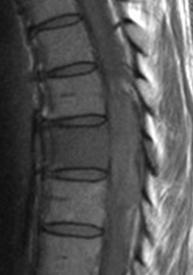

Intense homogeneous contrast enhancement

DWI Hyperintense

Periventricular lesions

Hyperdense lesion on nonconstast CT

Corpus callosum involvement